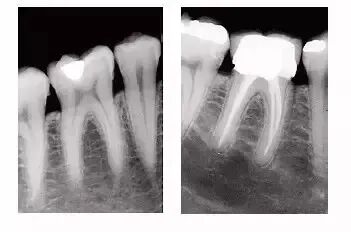

学习牙科x光的拍摄技术,就是玩光与影的艺术,拍摄出几张废片,并不可怕,要认真分析失败的原因,不断地摸索尝试,提高拍片洗片的质量。本期内容,我们将通过图文并茂的形式为大家详细讲解X光机的拍摄技术与心得。

上颌后牙X光拍摄的难点的原因分析:

A:我们人体的脸部肌肉密度非常大,颌骨的密度每个人的发达程度也不一样,人的面部侧方轮廓是有直面型,凸面型,凹面型,甚至有不规则型的。即使X光机器上有标准的刻度,但球管对面部的哪个投照体表标志会是更准确点呢?心里却是茫然的。拍摄后牙的厚度,比我们手掌的最厚部位还要厚3分之一呢!

B:牙科胶片固定于上颌后部的舌腭面,很多人咽部较为敏感,轻微的刺激就会恶心,流口水,咽部易感,影响拍摄。如果以上操作不正确,则尤甚,增加患者的痛苦,影响片子的质量!

牙科拍片的影响因素:

一个牙片的拍摄成功固然与拍摄的每一个步骤,甚至是机器的性能,电压,温度相关联。但成功的关键在于:

A:三个位置:1 头位(体位)是否正确?

2:片位是否正确?

3:X光的投照角度位置是否正确?

B:两个角度 心里要有两个角度的具体概念:垂直角度与平分角度

C:曝光时间的选择与控制

D;X光的摆放和固定

E:暗室或者明室的洗片技术